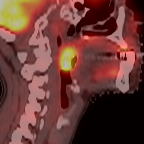

This paper presents an overview of the second edition of the HEad and neCK TumOR (HECKTOR) challenge, organized as a satellite event of the 24th International Conference on Medical Image Computing and Computer Assisted Intervention (MICCAI) 2021. The challenge is composed of three tasks related to the automatic analysis of PET/CT images for patients with Head and Neck cancer (H&N), focusing on the oropharynx region. Task 1 is the automatic segmentation of H&N primary Gross Tumor Volume (GTVt) in FDG-PET/CT images. Task 2 is the automatic prediction of Progression Free Survival (PFS) from the same FDG-PET/CT. Finally, Task 3 is the same as Task 2 with ground truth GTVt annotations provided to the participants. The data were collected from six centers for a total of 325 images, split into 224 training and 101 testing cases. The interest in the challenge was highlighted by the important participation with 103 registered teams and 448 result submissions. The best methods obtained a Dice Similarity Coefficient (DSC) of 0.7591 in the first task, and a Concordance index (C-index) of 0.7196 and 0.6978 in Tasks 2 and 3, respectively. In all tasks, simplicity of the approach was found to be key to ensure generalization performance. The comparison of the PFS prediction performance in Tasks 2 and 3 suggests that providing the GTVt contour was not crucial to achieve best results, which indicates that fully automatic methods can be used. This potentially obviates the need for GTVt contouring, opening avenues for reproducible and large scale radiomics studies including thousands potential subjects.